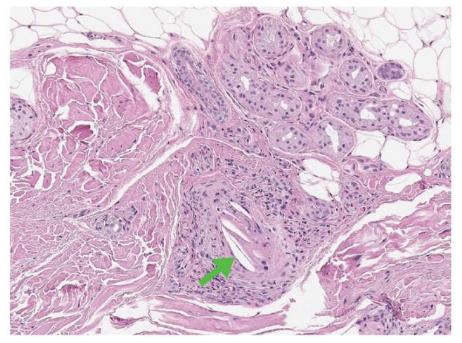

通过组织病理学检查可确诊:皮肤活检的诊断敏感性为41%;肌肉活检的诊断敏感性可达100%;单次肾活检的诊断敏感性达75%,重复活检的诊断敏感性达94%。典型病理改变为两面凸起的裂隙状胆固醇结晶阻塞小动脉管腔。本病例使用偏光显微镜观察到从股动脉获得的游离多层胆固醇晶体。

图2 68岁男性,全主动脉弓置换术和冠状动脉旁路移植术(CABG)术后足趾变蓝,对病变脚趾的皮肤进行活检发现了胆固醇结晶